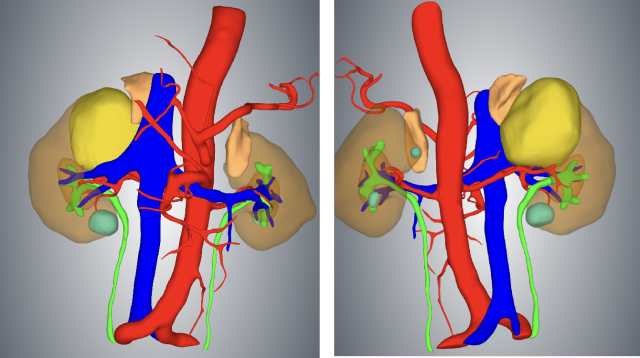

ECT 判断分肾功能

全身评价:胸部 CT 示双肺多发转移,转移不除外;ECT 肾功能显像示右肾功能中度受损